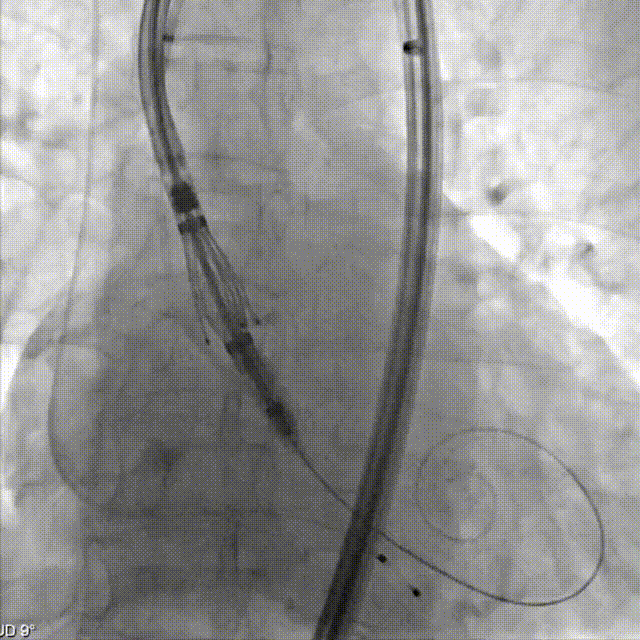

定位键与原生窦对齐

依次三窦内造影确认深度

患者深度镇静后超声引导下建立入路,跨瓣后左室放置预塑形导丝,使用TaurusTrio系统定制的等效于18F超长导引鞘定位STJ。输送系统装载THV27瓣膜,在大鞘保护下从右股动脉送入,安全通过降主动脉及钙化弓顶。在右窦中心位下,回撤导引鞘远端至降主动脉后定位键展开,使用调弯功能改善瓣膜同轴性,DSA下观察THV从大弯侧调至居中,再通过旋转定位手柄在右窦中心位下调整三个定位键与原生窦一一对齐,后推进THV使定位键进入窦底,实现Commissural alignment,通过造影依次确认无、右、左窦内定位键及深度后,最终脱钩释放。术后即刻超声心动图评估显示瓣膜位置良好,无瓣周漏,无中心反流,血流动力学指标优异。